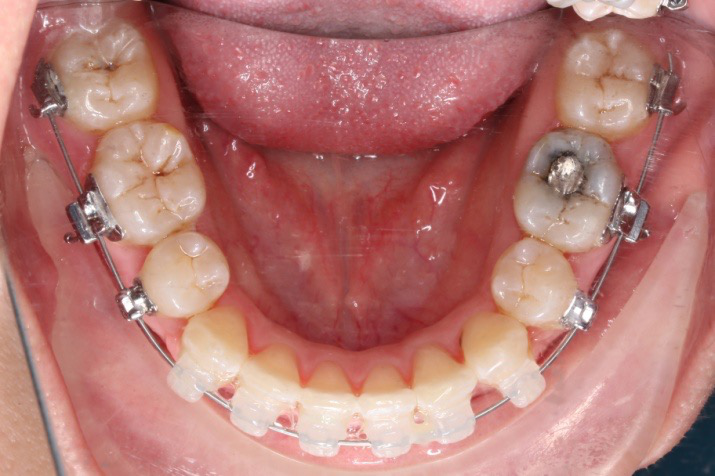

2017.05.26  磨牙近中倾斜,下颌36、46加power arm

下颌磨牙通过powerarm直立效果明显,下颌整平效果明显

下颌整平内收的生物力学

下前牙的压低+控制性倾斜移动内收,改善唇倾度,磨牙通过powerarm 直立,控根整体近中移动,使咬合高点的前移,整平下颌同时进行内收。

下后牙: 向前,整体移动利于咬合支点前移(Power arm);▲向前,倾斜移动易导致咬合平面后下旋转;▲后牙压低/全牙弓压低利于咬合平面逆时针旋转。